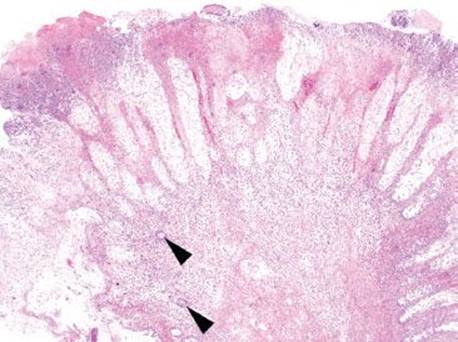

Figure 4.85 Pseudomembranous pattern. The crypt epithelium begins to slough and the lamina propria is edematous. The surface shows abundant fibrin and acute inflammatory cells.

Figure 4.87 Pseudomembranous pattern. A dramatic (and beautiful) example of an eruptive pseudomembrane. The extensive fibroinflammatory debris appears to erupt from a single crypt (arrowhead).